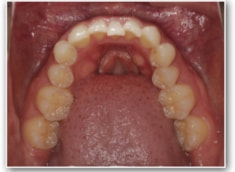

治療前